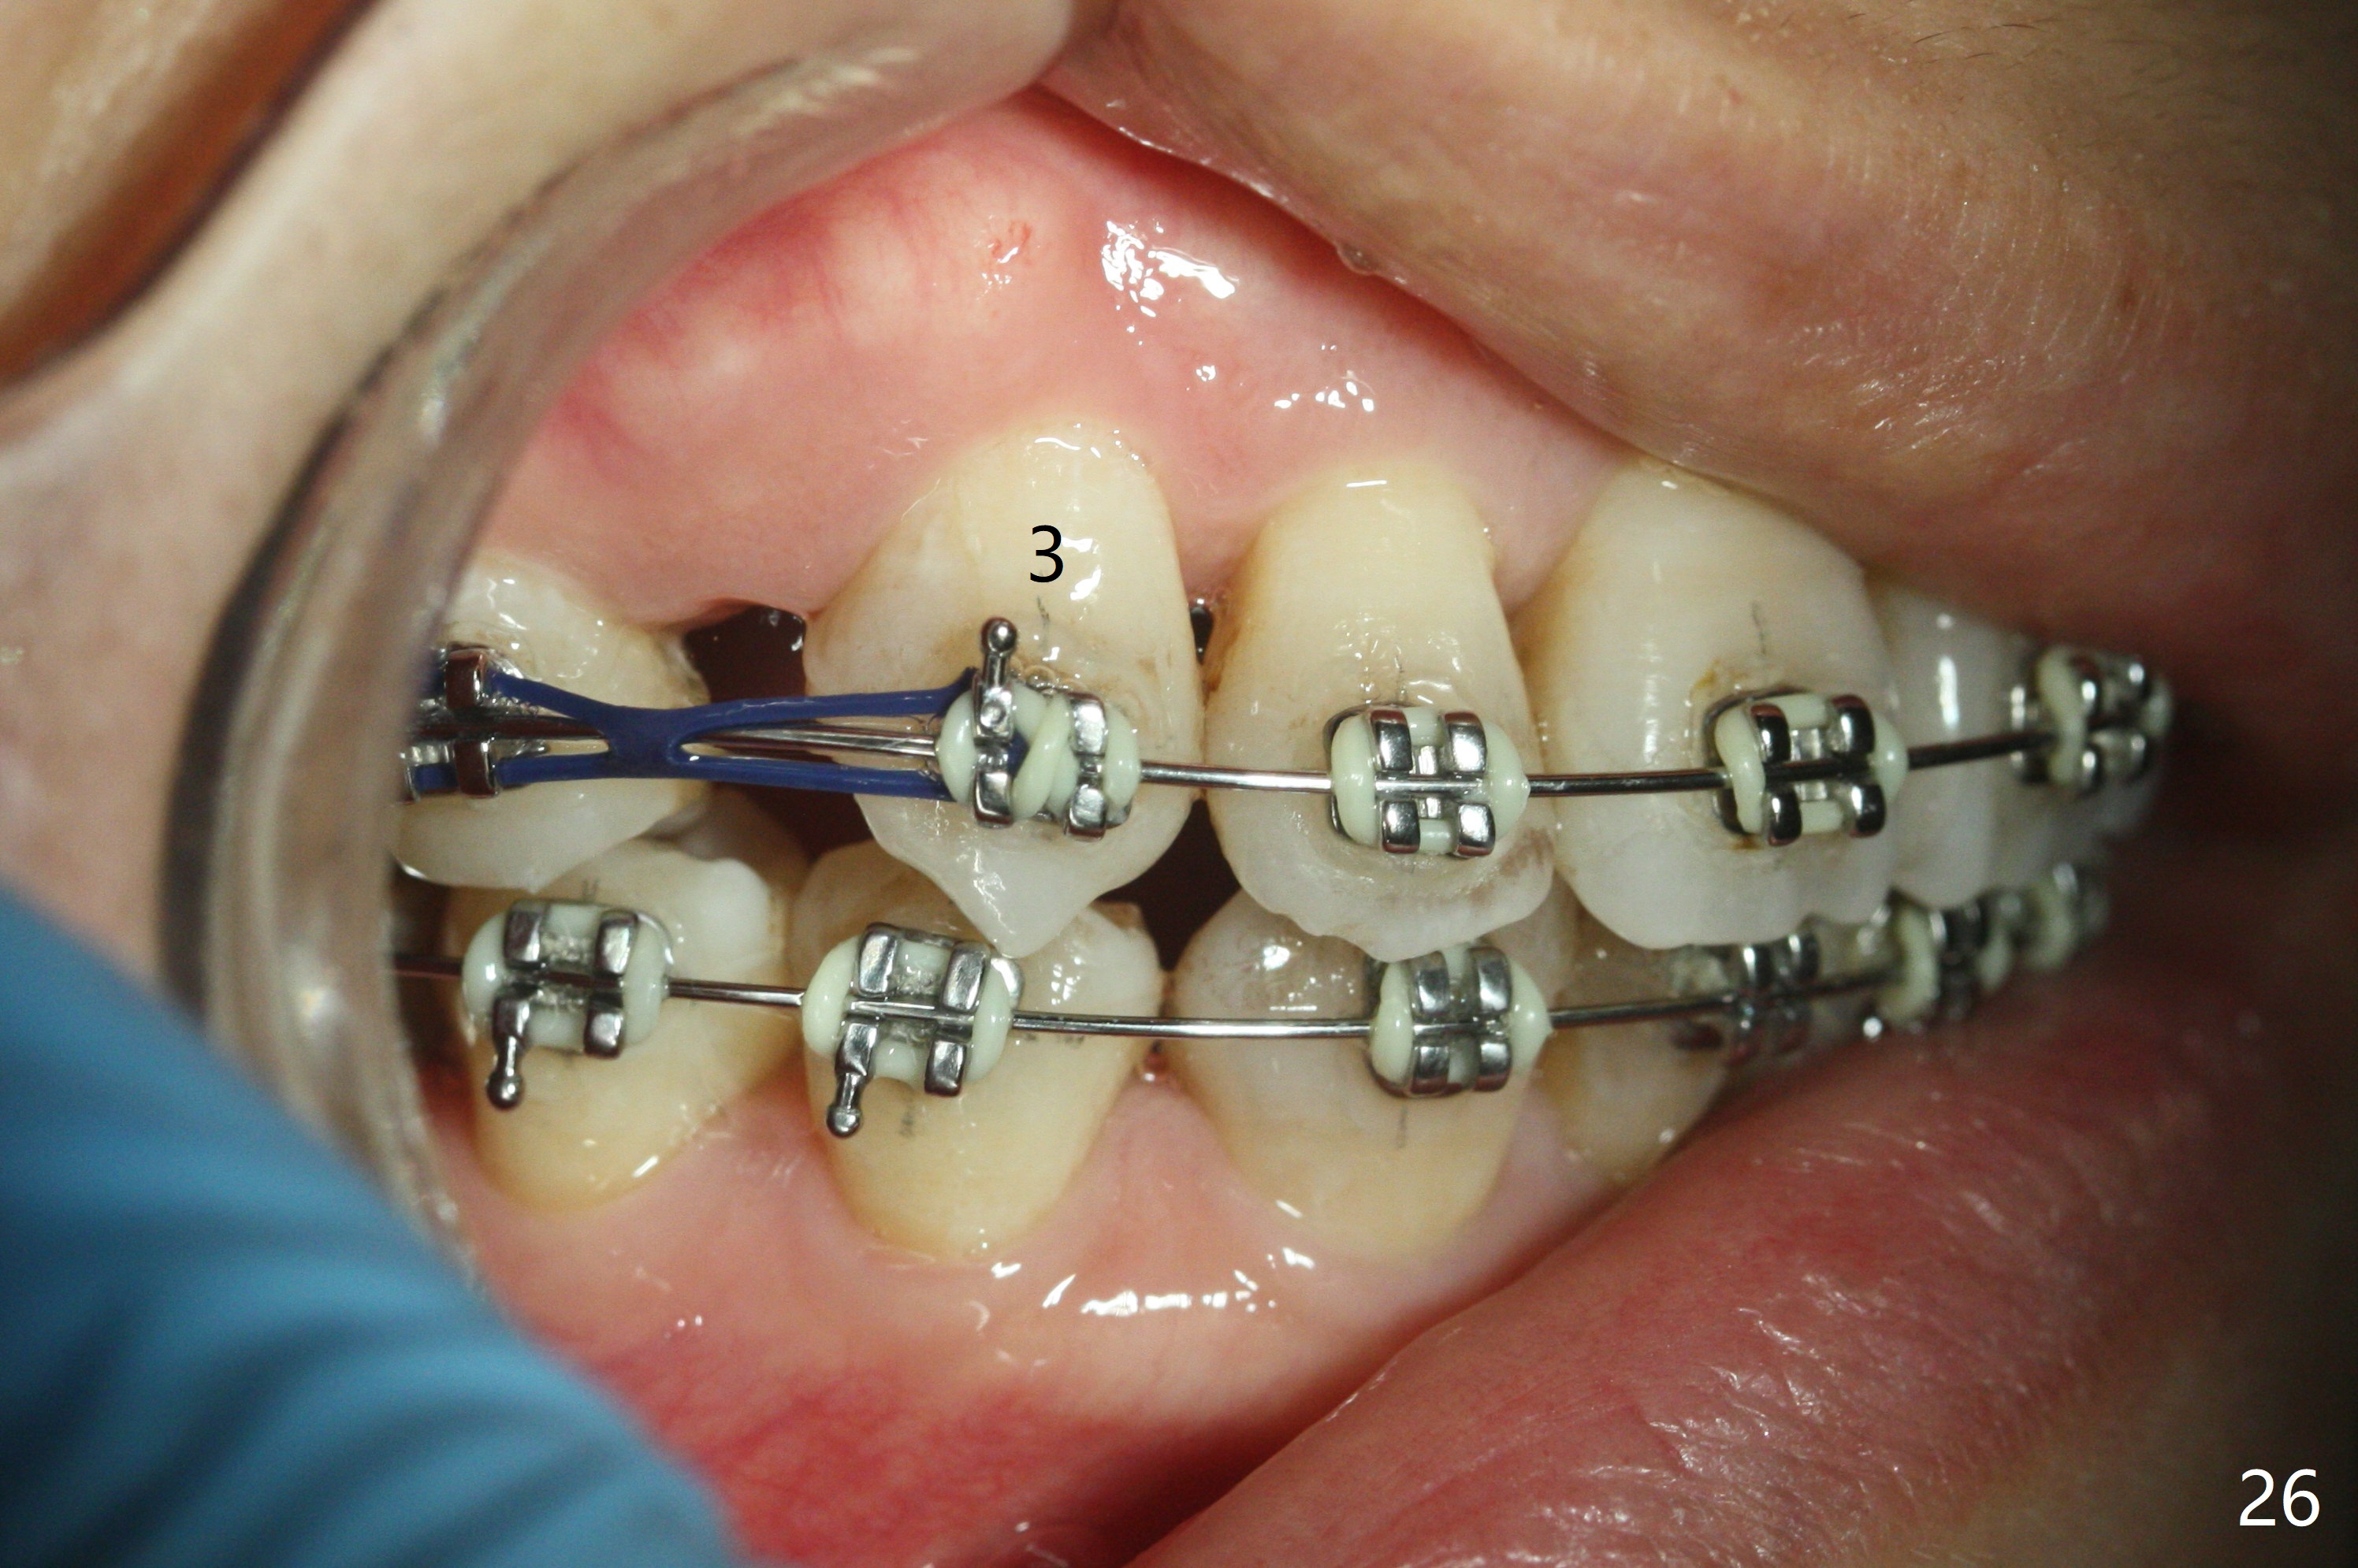

Eight months post banding, UR3 appears to be distalized with de-rotation (Fig.26), while UL3 is slightly over-distalized with mesial space (Fig.27 arrow). LL5 remains rotated (Fig.28). One months later, anterior over bite and over jet seem to be normal. In spite of lack of Class I anterior occlusion, it is decided that the upper posterior teeth should be mesialized. Next visit, wires will be changed to 16x16 with ligature wire between U3-3 and power chains between U3 and 5.